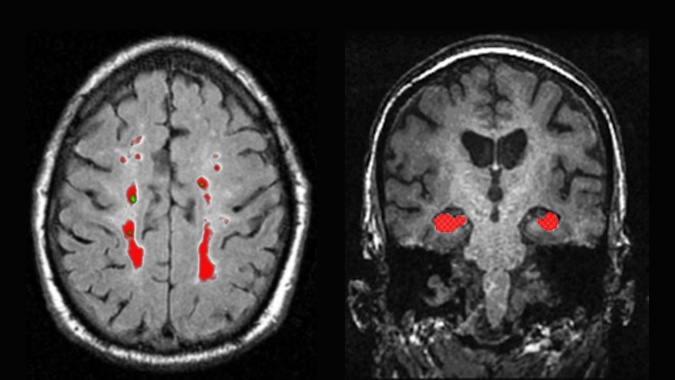

Aberdeen Birth Cohorts Brain Ageing Research

In collaboration with the research groups led by Professors Alison Murray and David Lurie at the Aberdeen Biomedical Imaging Centre, we are continuing innovative imaging research. We aim to conduct translational research though this multidisciplinary work which will have major impact on understanding of brain ageing, cognitive resilience and pathophysiology of dementias.